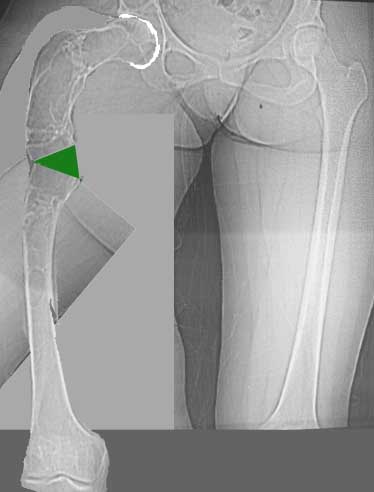

Женщина 28 лет, Больна с 12 летнего возраста, Когда после адекватной травмы получила перелом бедра. На рентгенограммах выявлено какое-то (рентгенограмм и документов нет) изменение бедренной кости, была оперирована, имеется гистологическое заключение - фиброзная дисплазия.дСформировалась деформация бедра. На сегодня - Укорочение 7см. Грубая деформация бедра по типу "пастушьей палки", последний патологический перелом в январе 2004г., консолидировавшийся при консервативном лечении. Имеются грубые изменения и в надвертлужном массиве.-- С уважением, Leonid

Возможна аппаратная коррекция оси с формированием клиновидного регенерата, которая решила бы и проблему укорочения (что, впрочем, нужно уточнить по схеме, сделанной по рентгенограмме с хорошим захватом смежных суставов - схемка по присланному снимку в приложении). По окончании коррекции - блокируемый стержень, который и сократит время пребывания в аппарате, и вообще возврата к нормальной жизни, а также будет мерой профилактики патологических переломов.

Собственно сустав не беспокоит, объем движений полный. По скиаграммам получается, что достаточно одной остеотомии на вершине деформации, чтобы восстановить длину и вывести коленный сустав в нужное положение.

Т.к. укорочение 7 см, то начинать будем с соеотомии и коррекции аппаратом. Спасибо